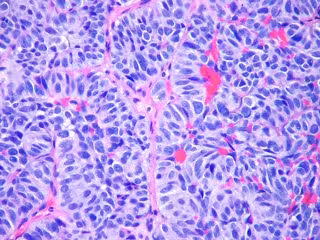

Metástasis pulmón

FLICKR/PULMONARY PATHOLOGY/ CC BY-SA 2.0 - Archivo